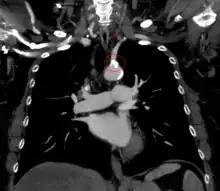

![]() | |

The proximal part of left subclavian is blocked (shaded artery). This prevents antegrade ("forward") flow to the left arm and left vertebral. As a result, flow in the left vertebral is retrograde ("backwards") towards the left arm. Flow to the brain and circle of Willis is via antegrade right and left carotid and right vertebral arteries. | |